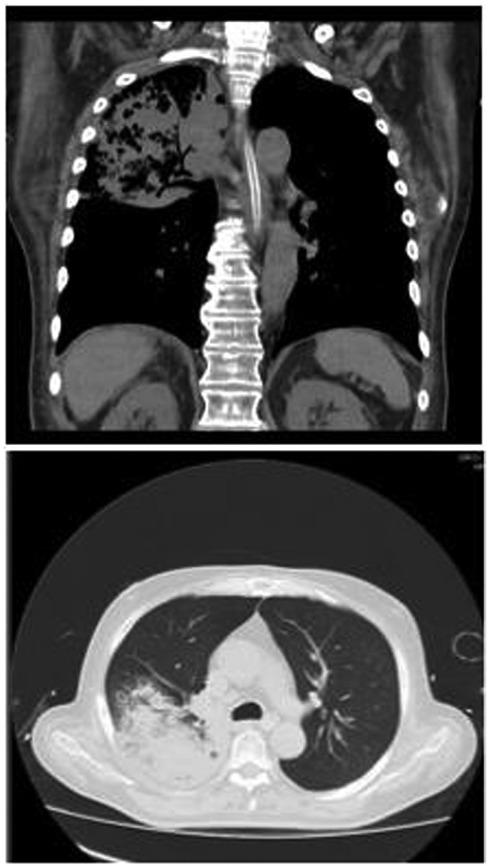

Figure 1